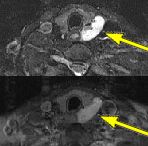

Fig.1 Fig.2 Fig.3 Fig.4

FINDINGS: The ultrasound (not shown) revealed a large solid mass behind the left lobe of the thyroid. Fig. 1-2 are MRI images of the neck demonstrating a mass behind the left thyroid lobe with hyperintensity on T2 weighted and STIR images (Fig. 1, 2 top) and enhancement higher than the thyroid (Fig. 2 bottom). Fig. 3-4 are Sestamibi images with Fig. 3 being coronal (top) and axial (bottom) SPECT images and Fig. 4 the early and delayed static images demonstrating persistent activity in the mass on delayed images while the thyroid activity washes out (arrows).

ABNORMAL SCAN: A parathyroid adenoma also demonstrates rapid uptake on the initial images. However, unlike a normal thyroid, the adenoma demonstrates persistent uptake of Sestamibi and is readily visible on delayed images. Ectopic adenomas in the mediastinum are also easily detected with this technique.